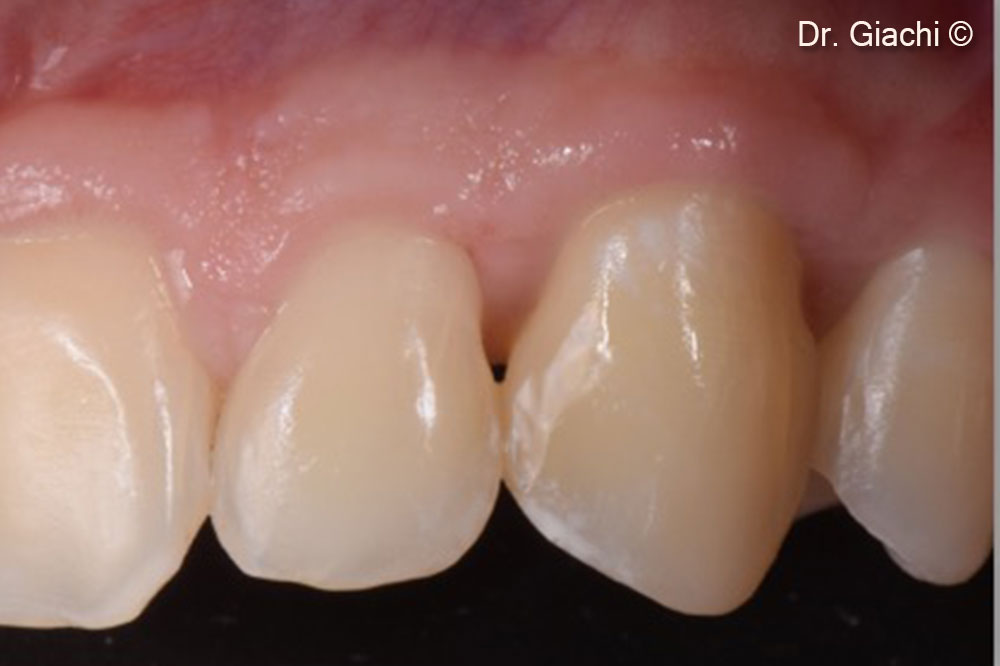

Một bệnh nhân nam (16 tuổi) có răng nanh trên không thể phục hồi bằng phương pháp chỉnh nha truyền thống.